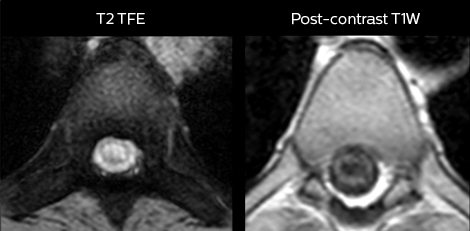

cervical spine mri in ed

Cervical spine routine exam

This patient presented with headache that was worse with neck flexion and we see a Chiari 1 malformation with low-lying cerebellar tonsils as well as some degenerative cervical thrombolytic change.